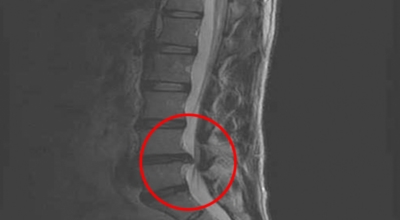

디스크는 일어선 상태에서는 중력을 받아 납작해져서 바깥쪽으로 약간 볼록한 형태가 된다고 합니다. 디스크는 그 특수한 구조 때문에 웬만한 힘이 가해져도 효율적으로 쿠션 역할을 할 수 있겠습니다. 그러나 급작스럽게 무거운 물건을 들어 올리거나, 부자연스러운 자세를 오랜 시간 취하면 디스크에 무리한 힘이 가해지면서 디스크가 밖으로 돌출이 되게 돼요. 심한 경우 디스크를 감싼 막이 터지면서 그 안에 있는 수핵이 튀어나오게 돼요.

디스크는 대개 후방이나 후외방으로 돌출되는데 이때 바로 곁에 있는 신경을 누르게 된다고 합니다. 돌출된 디스크는 척추의 어느 부위에나 일어날 수 있어요. 목에 생기면 '목 디스크', 등에 생기면 '등 디스크', 허리에 생기면 '허리 디스크'라고 부른다고 합니다.

이와 같이 디스크가 돌출되어 신경을 눌러 요통 또는 다리가 아프고 저린 증상을 유발하는 병을 '추간판 탈출증' 및 '디스크 탈출증'이라고도 불러요. 발생 빈도별로 보면 허리 디스크가 가장 흔합니다. 그다음이 목 디스크이지요. 등 디스크는 드문 병이라고 합니다.